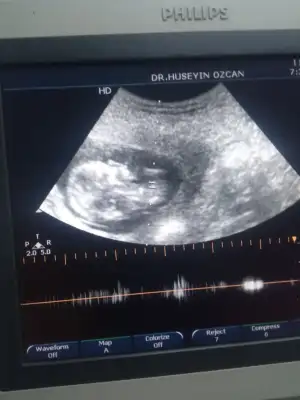

Ikra meyra Ikra meyra Canım merhaba 10. Haftamda bakmıştın erkek , emin olmak için 12. Haftada bakalım demiştin 13+0 karından ultrason fotomuzu atıyorum halen fikrin aynı mı ? Teşekkür ederim 💕

Merhaba 12 haftalık arkadaşımin tahminin varmi